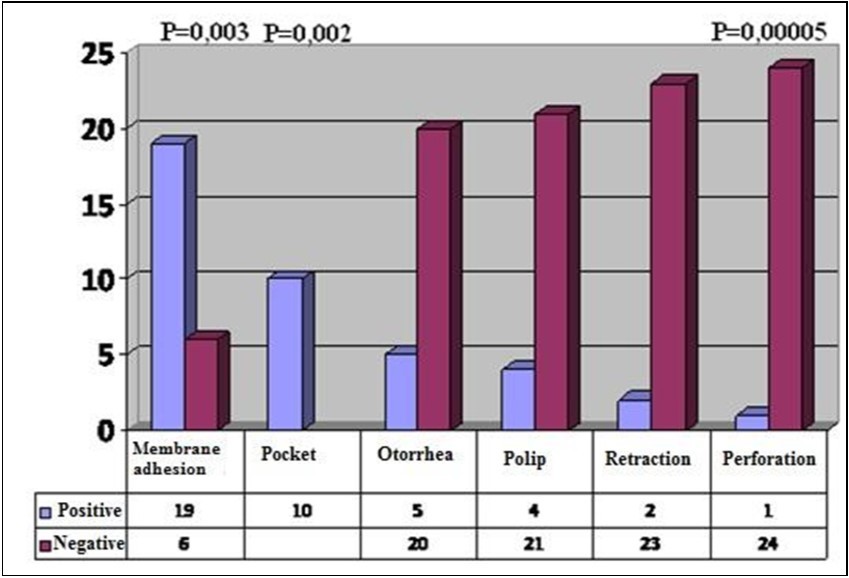

| Adhesion Positive (n) Negative (n) | 19 (95%) 6 (46.2%) | 1 (5%) 7 (53.8%) | 0.003 |

| Retraction Pocket Positive (n) Negative (n) | 16 (100%) 9 (52.9%) | - 8 (47.1%) | 0.002 |

| Otorrhea Positive (n) Negative (n) | 5 (100%) 20 (71.4%) | - 8 (28.6%) | 0.22 |

| Polipoid Tissue Positive (n) Negative (n) | 4 (100%) 21 (72.4%) | - 8 (27.6%) | 0.30 |

| Retraction Positive (n) Negative (n) | 2 (66.7%) 23 (76.7%) | 1 (33.3%) 7 (23.3%) | 0.70 |

| Perforation Positive (n) Negative (n) | 1 (14.3%) 24 (92.3%) | 6 (85.7%) 2 (7.7%) | 0.00005 |

Presence of membrane adhesions (p= 0,003) and retraction pockets (p=0,002) on preoperative examination were considered to be statistically significant in terms of observing intaoperative cholesteatoma. Patients with dry perforations (p=0,00005) did not demonstrate intraoperative cholesteatoma (Figure 1) (Table 1).

Figure 1.Physical examination findings and presence of cholesteatoma